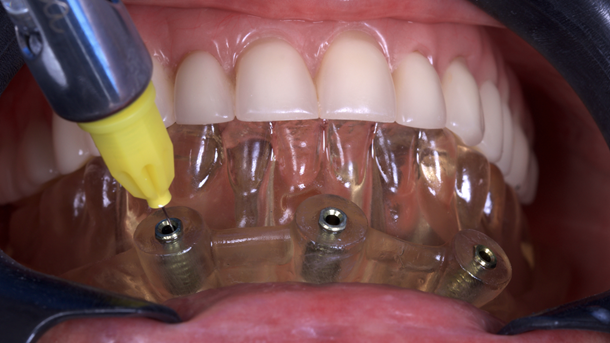

O guia foi fixado após estabilização em oclusão com a prótese superior. Após a retirada do guia de oclusão, foi fixada a guia de fresagem e instalação dos implantes, que foram instalados com torques superiores a 32N, o que permitiu a captura imediata da prótese provisória através do pilar de titânio e resina de fluxo.

O tempo do procedimento desde a anestesia até a finalização da prótese provisória foi de 2h10.